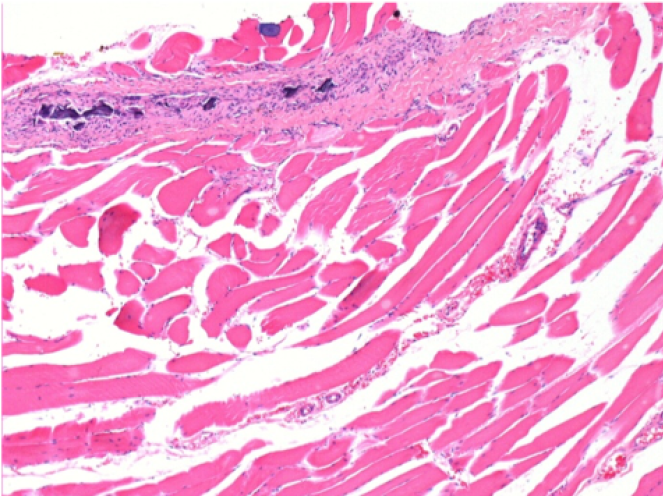

7 months after Endopeel Injection

7 months (D210)after Endopeel IM Injection 0.1ml in the right pretibial muscle.

Complete Restitutio ad integrum after 7 months

L : Control-100xD210

R:100xD210

L :Control 50xD210

R50X-D210